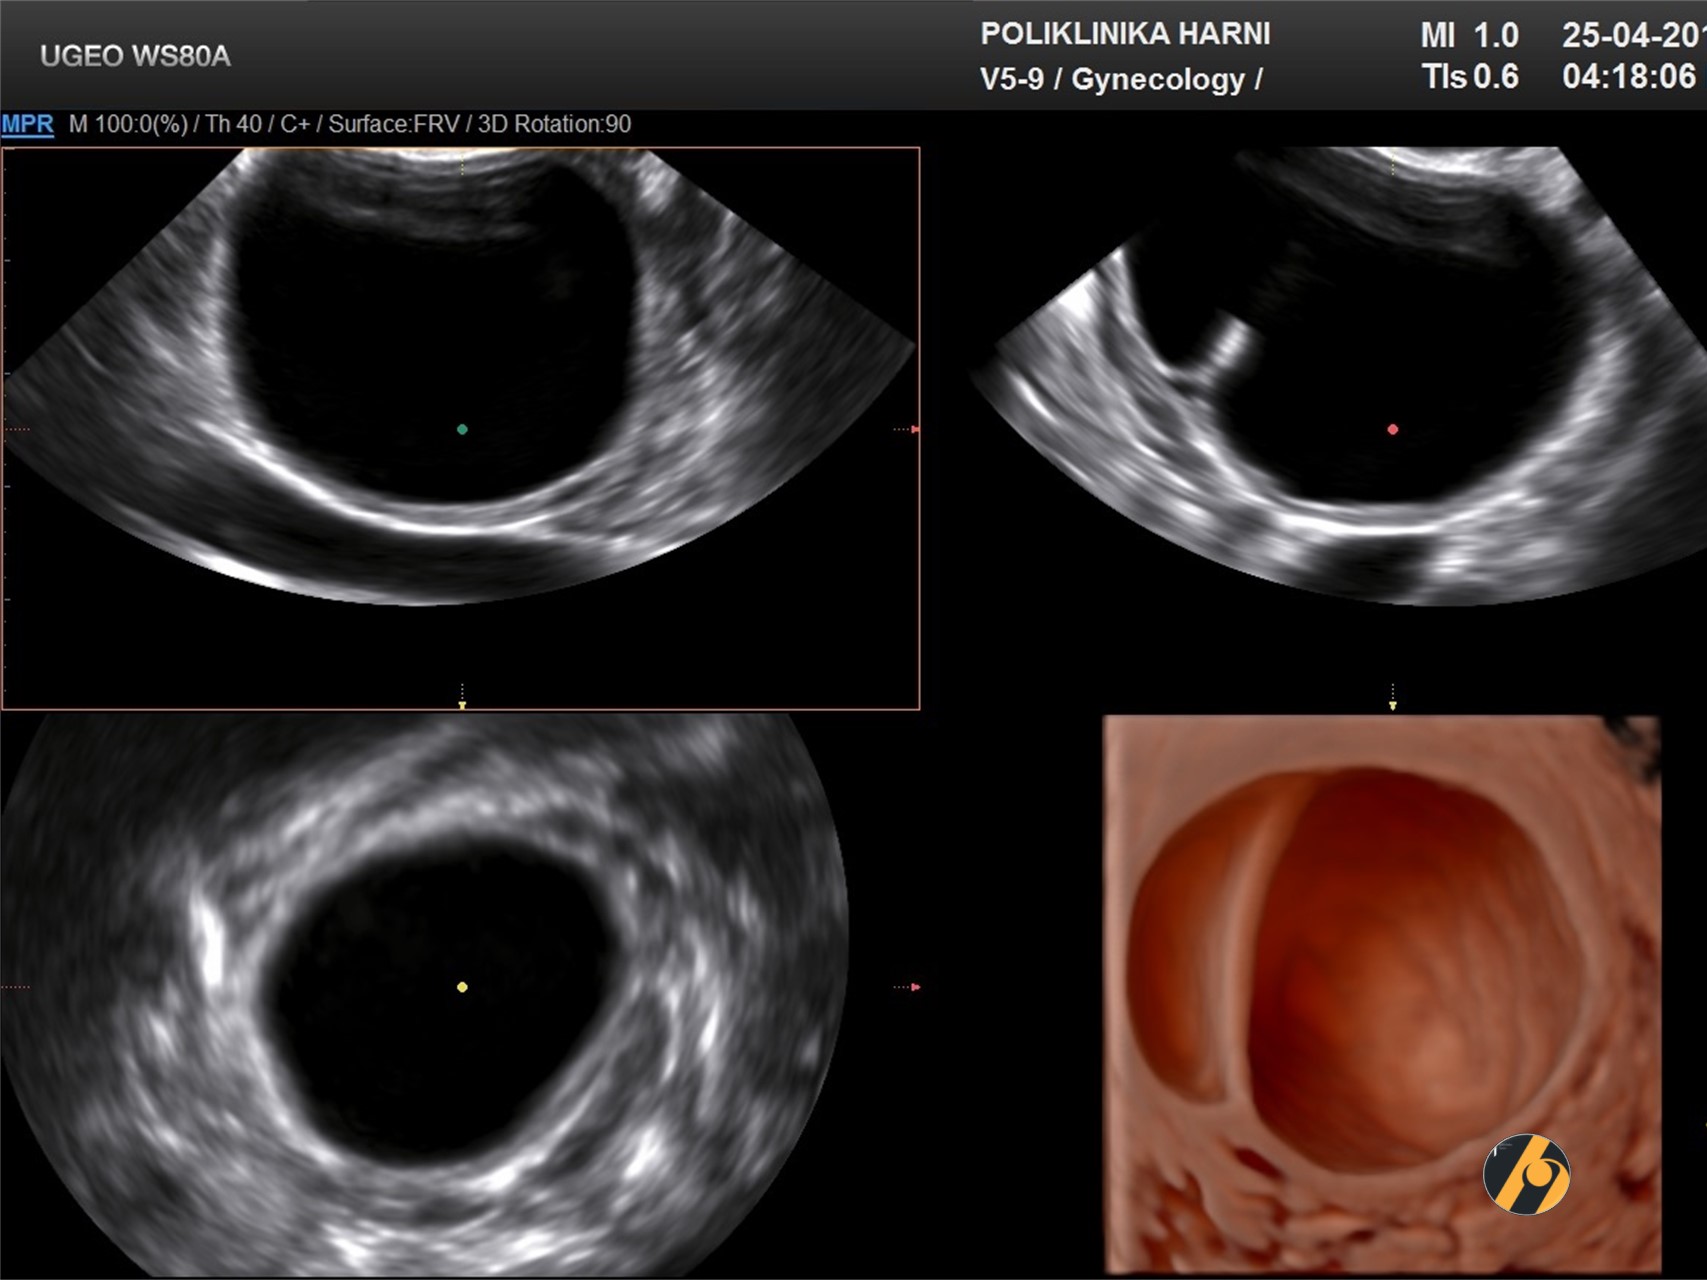

Jednostavne ciste jajnika, koje se otkrivaju zdjeličnim ultrazvukom, nisu povezane s povećanim rizikom za rak jajnika i ne treba ih ultrazvučno pratiti, prema novoj studiji. Današnjim ultrazvučnim tehnikama je moguće dobro procijeniti nalaz sumnjihivih detalja kao štu su debele, vaskularizirane pregrade ili proliferacije unutar cista, a dopleskim mjesrenjima se nalaze nove atipične krvne žile. Pored toga, u evaluaciji ovih tvorbi postoje dobri krvni testovi, pa je u nekim slučajevima određivanje i praćenje kretanja razine tumorskih biljega vrlo važan dio praćenja ovih pacijentica.

Međutim, ako ultrazvuk otkriva složenu cistu ili čvrstu masu, rizik od raka jajnika je značajno povišen, takvi slučajevi zahtijevaju pažljivo praćenje, zaključuje istraživanje .Danas postoje dobri ultrazvučni kriteriji, poput IOTA ili GI RADS sustava, koji nam mogu pomoći da relativno brzo odlučimo koja pacijentica spada u rizičnu skupinu koju valja nadzirati.

Jednostavne ciste su česte, javljaju se u žena u pre i postmenopauzi. Dobro je poznato da ove ciste nastaju iz funkcionalnih cista, folikuliranih ili luteinskih cista koje se svaki mjesec stvaraju u jajnicima. Dovoljna su minimalna odstupanja u hormonskom sustavu koja remete pravilno pucanje folikularne ciste ili pravilnu apoptozu luteinske ciste, kada iz njih nastaju jednostavne ciste. Ove ciste, prema novim istraživanjima, ne zahtijevaju ultrazvučni nadzor svakih 6 ili 12 mjeseci, piše glavni autor Rebecca Smith-Bindman, University of California, Berkeley.